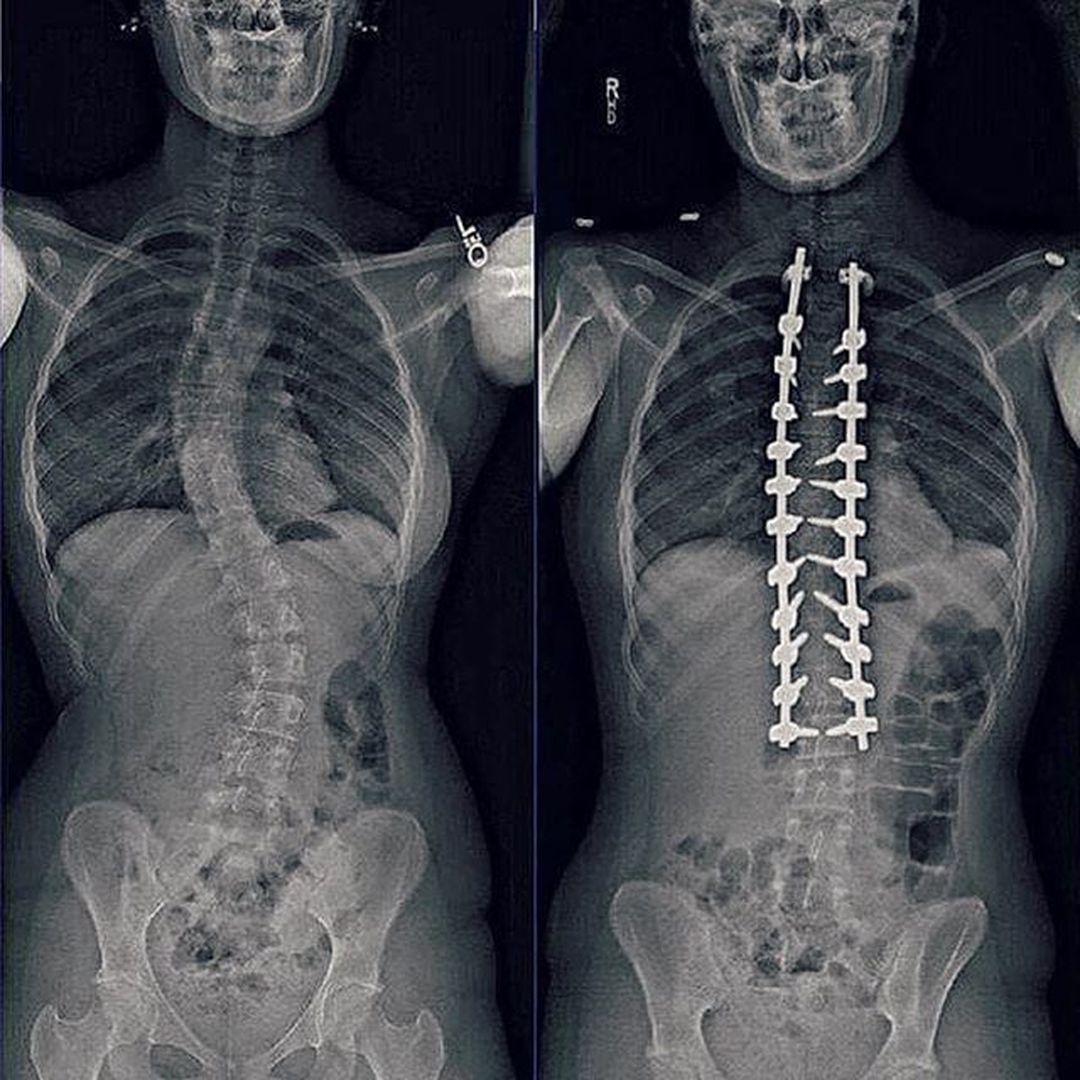

Preoperative (Before surgery) and Postoperative (After surgery) case of scoliosis